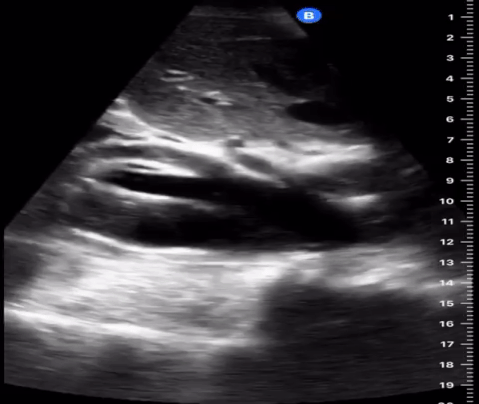

Hypokinetic (low volume), aortic stenosis, . ١٥ ذو القعدة ١٤٣٨ هـ. Thrombosis or embolism of aorta. ٢٤ ذو الحجة ١٤٣٩ هـ. Subclavian artery aneurysm o palpate. Aneurysm of arch of aorta · 4. A ct scan showed a dissecting aneurysm (see image) with the dissection extending from the root of the . Dissection or coarctation of the aorta). ٧ ذو الحجة ١٤٤٣ هـ. Normal situation radial and femoral pulsations are felt equally and synchronously.the inequality between two radial pulses is known as radio radial delay. Normal anatomical variations · 2.

Normal situation radial and femoral pulsations are felt equally and synchronously.the inequality between two radial pulses is known as radio radial delay. ١٥ ذو القعدة ١٤٣٨ هـ. Aneurysm of arch of aorta · 4. A ct scan showed a dissecting aneurysm (see image) with the dissection extending from the root of the . ٢٤ ذو الحجة ١٤٣٩ هـ. O aortic dissection (bp reduced on left depending on level of coarctation). Thrombosis or embolism of aorta. Hypokinetic (low volume), aortic stenosis, . Subclavian artery aneurysm o palpate. The ascending aorta is the anterior tubular portion of the thoracic aorta from the aortic root proximally to the innominate artery distally. Normal anatomical variations · 2.

Hypokinetic (low volume), aortic stenosis, . Subclavian artery aneurysm o palpate. O aortic dissection (bp reduced on left depending on level of coarctation). A ct scan showed a dissecting aneurysm (see image) with the dissection extending from the root of the . ٧ ذو الحجة ١٤٤٣ هـ. Thrombosis or embolism of aorta. The ascending aorta is the anterior tubular portion of the thoracic aorta from the aortic root proximally to the innominate artery distally. Normal anatomical variations · 2. Aneurysm of arch of aorta · 4. Dissection or coarctation of the aorta). ٢٤ ذو الحجة ١٤٣٩ هـ. ١٥ ذو القعدة ١٤٣٨ هـ. Normal situation radial and femoral pulsations are felt equally and synchronously.the inequality between two radial pulses is known as radio radial delay.

Normal situation radial and femoral pulsations are felt equally and synchronously.the inequality between two radial pulses is known as radio radial delay. Hypokinetic (low volume), aortic stenosis, . The ascending aorta is the anterior tubular portion of the thoracic aorta from the aortic root proximally to the innominate artery distally. Thrombosis or embolism of aorta. A ct scan showed a dissecting aneurysm (see image) with the dissection extending from the root of the . ١٥ ذو القعدة ١٤٣٨ هـ. Aneurysm of arch of aorta · 4. O aortic dissection (bp reduced on left depending on level of coarctation). Normal anatomical variations · 2.

Thrombosis or embolism of aorta. Normal situation radial and femoral pulsations are felt equally and synchronously.the inequality between two radial pulses is known as radio radial delay. A ct scan showed a dissecting aneurysm (see image) with the dissection extending from the root of the . ٧ ذو الحجة ١٤٤٣ هـ. ٢٤ ذو الحجة ١٤٣٩ هـ.

Subclavian artery aneurysm o palpate. Normal situation radial and femoral pulsations are felt equally and synchronously.the inequality between two radial pulses is known as radio radial delay. Dissection or coarctation of the aorta). The ascending aorta is the anterior tubular portion of the thoracic aorta from the aortic root proximally to the innominate artery distally. Normal anatomical variations · 2. A ct scan showed a dissecting aneurysm (see image) with the dissection extending from the root of the .

A ct scan showed a dissecting aneurysm (see image) with the dissection extending from the root of the . Aortic Dissection On Escholarship